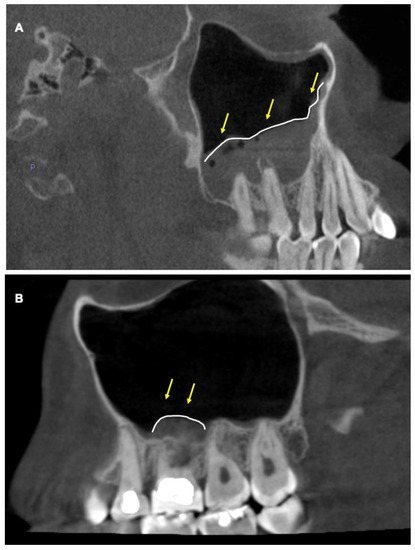

- Cymerman, J.J.; Cymerman, D.H.; O’Dwyer, R.S. Evaluation of odontogenic maxillary sinusitis using cone-beam computed tomography: Three case reports. J. Endod. 2011, 37, 1465–1469. [Google Scholar] [CrossRef]